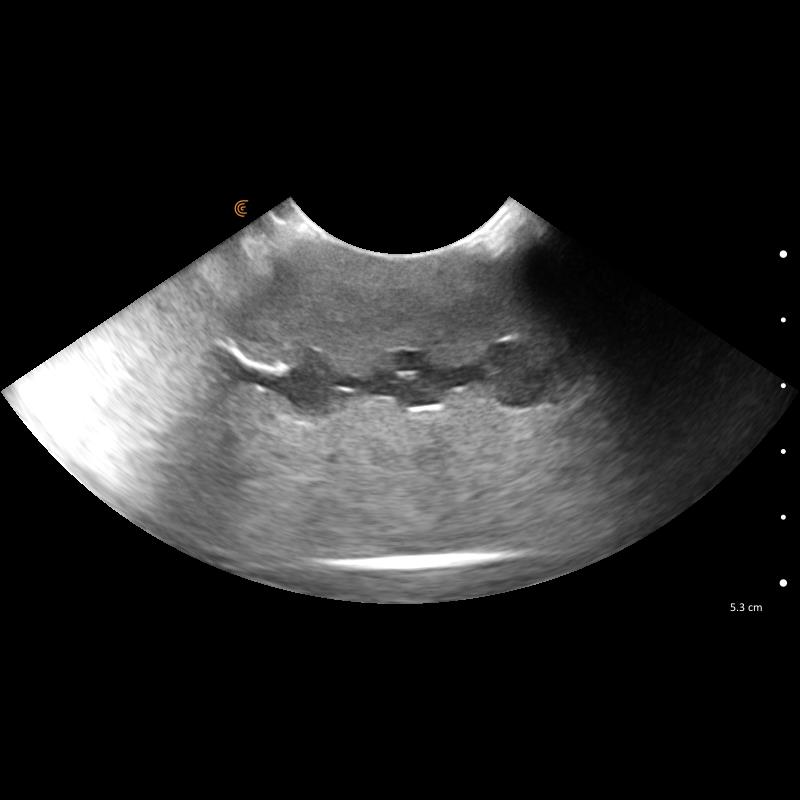

Le kit de formation fantôme à l’échographie canine "Lillie" Erler Zimmer est un outil indispensable pour la formation et la pratique en échographie vétérinaire. Conçu pour reproduire fidèlement l’anatomie canine, il permet aux professionnels de Santé vétérinaires, étudiants et praticiens expérimentés de s’entraîner de manière réaliste sur tous les organes majeurs : cœur, poumons, foie, pancréas, reins, intestins et système vasculaire.

Ce kit complet inclut le module “Skills”, qui enrichit l’apprentissage en proposant des structures anéchogènes, nodules hyperéchogènes et zones d’évaluation, idéales pour simuler des situations cliniques complexes. Le bloc FNA auto-réparant offre la possibilité de pratiquer des ponctions et gestes interventionnels en toute sécurité, garantissant un entraînement répétitif sans patient vivant.

Simulation complète des organes canins : cœur, poumons, foie, pancréas, reins, intestins, vessie et vaisseaux majeurs.

Module “Skills” avancé : nodules, structures anéchogènes et échogènes, vaisseaux spiraux pour un entraînement ciblé.